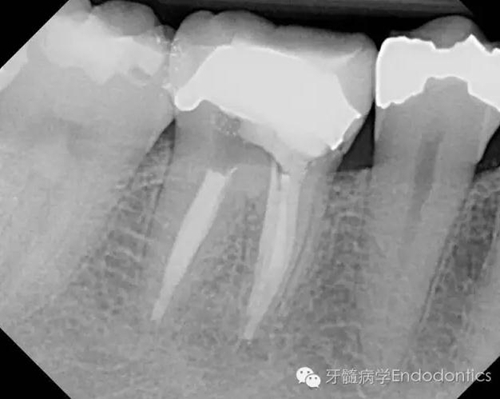

圖2.術(shù)前X線片(b)